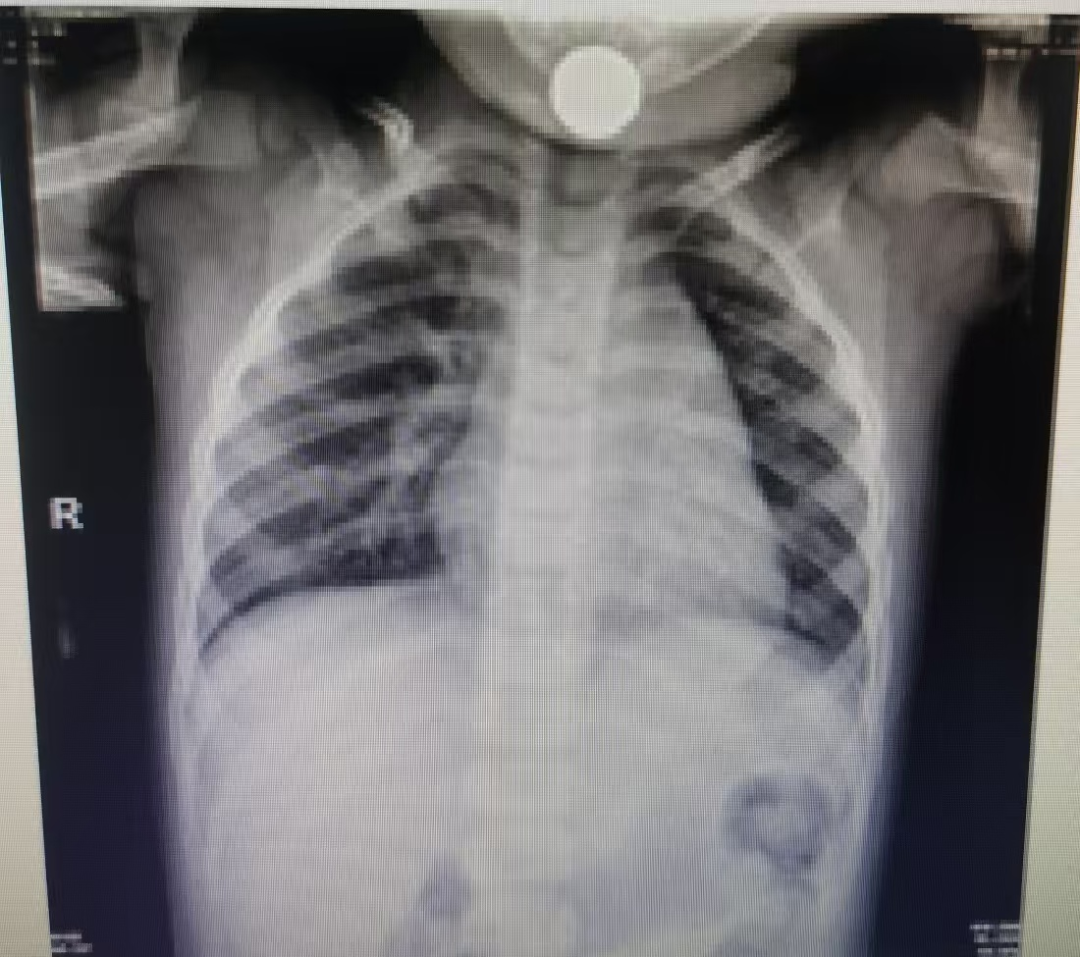

急诊X光检查清晰显示——硬币嵌顿于食管上段(相当于第5-6颈椎水平),该位置解剖结构复杂且狭窄。